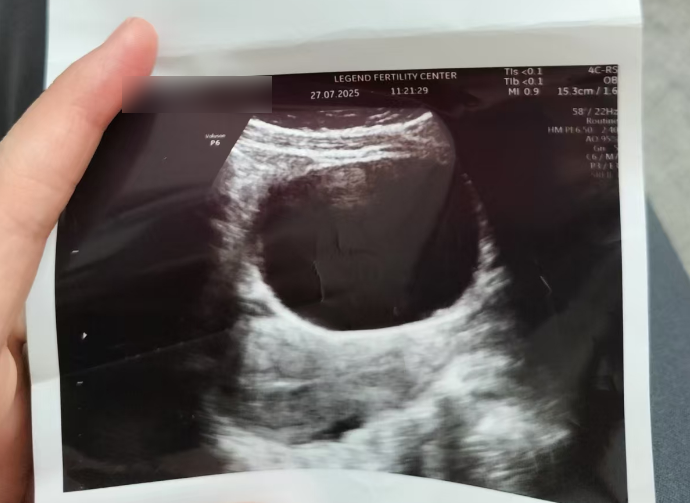

经过5天调理,7月27日,H女士的内膜终于达标,清晰“三线征”出现,激素水平也适配胚胎着床。

吉蒂亚医生果断安排移植,这一步,每一个细节都关乎成败。